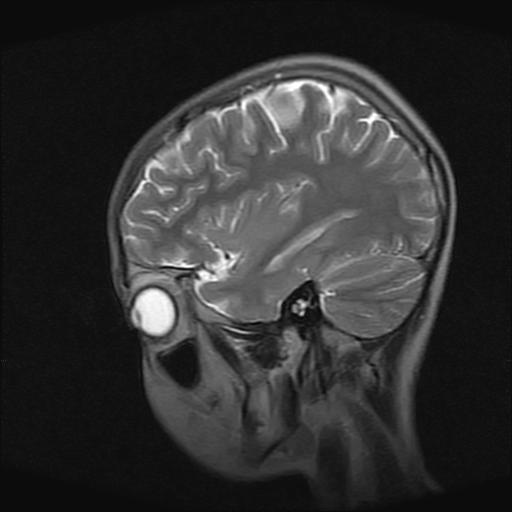

9岁女孩,三岁时诊断为癫痫,一直服丙戊酸钠,现患者一般情况良好,家长复查核磁片,看能否停药..

巨脑回